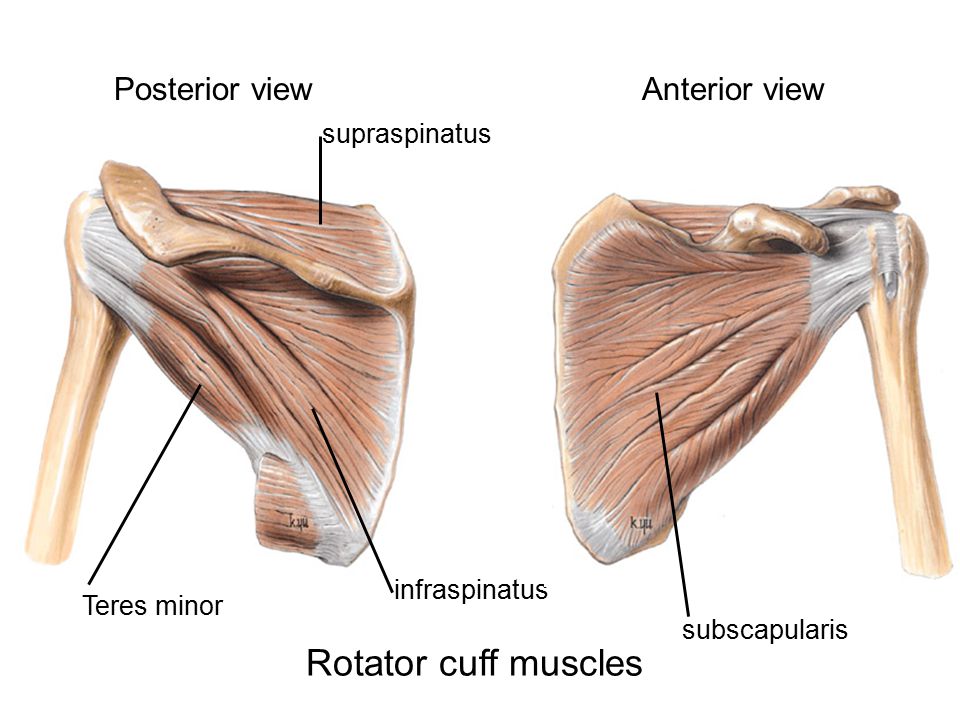

Фотографии мышц ротаторной манжеты плеча